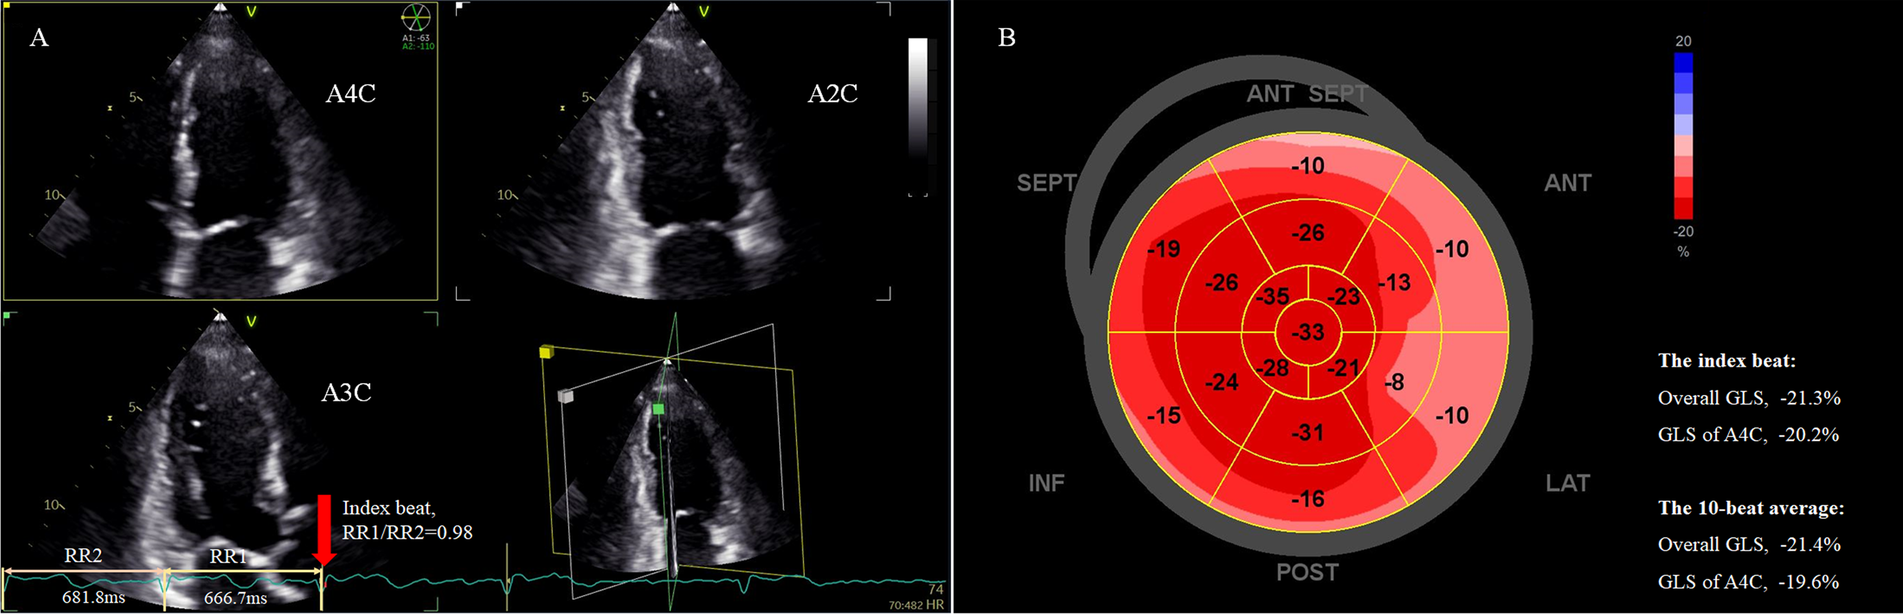

Figure 2

Assessment of LV overall GLS in a patient with persistent AF using the index beat. (A) Strain analysis was performed based on triplane echocardiography showing simultaneous apical two-, three-, and four-chamber views. The index beat (red arrow) was defined as the beat with an almost equal preceding (RR1) and pre-preceding (RR2) R-R intervals. (B) The bull's-eye plot of regional GLS. The overall GLS value and GLS of the atrial four-chamber view of the index beat closely matched the 10-beat average value. AF, atrial fibrillation; GLS, global longitudinal strain; LV, left ventricle.

STE analysis was performed using a commercially available software (EchoPAC V204, GE). Strain was calculated as the percentage change in end-systolic length/initial length. GLS was measured from standard apical two-, three-, and four-chamber views of the triplane dataset (Figure 2). The bull’s eye of segmental peak longitudinal strain with sectional GLS, overall GLS of 17 segments, and heart rate for each beat could be obtained (Figure 2B). Measurements were performed beat-by-beat for 10 consecutive beats, and mean apical four-chamber GLS and overall GLS over these 10 beats were calculated for analysis, as these parameters are most frequently used in clinical practice. For each heartbeat, the R-R interval (ms) was calculated as 60,000 divided by the heart rate (bpm), the latter obtained automatically from the analysis software. For example, if the heart rate for a selected cycle was 60 bpm, the R-R interval would be 60,000/60 = 1,000 ms. The index beat was defined as the beat with nearly equal preceding (RR1) and pre-preceding (RR2) intervals (Figure 2A). Because a ratio of RR1/RR2 exactly equal 1.0 is difficult to obtain in AF, we accepted a range of 0.96–1.04 as eligible (17). The GLS values for both the apical four-chamber view and overall GLS from the index beat were extracted for analysis. The echocardiographer performing the initial measurements was blinded to both the average MW over 10 beats and the index beat for each patient. An index beat-derived overall GLS was considered representative if its absolute difference from the 10-beat average was within 5%.